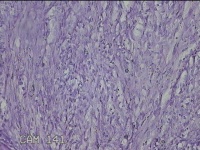

左大腿皮下结节

性别

女

年龄

30岁

临床诊断

皮下结节

一般病史

发现左大腿皮下结节1年余。

标本名称

大体所见

灰白粉红色组织1.7x0.8x0.3cm一个,表面带梭形皮肤 1.3x0.7cm,皮下见结节1.7x0.7cm一个,切开结节呈实性,切面灰白灰白粉红色,质中。

图1